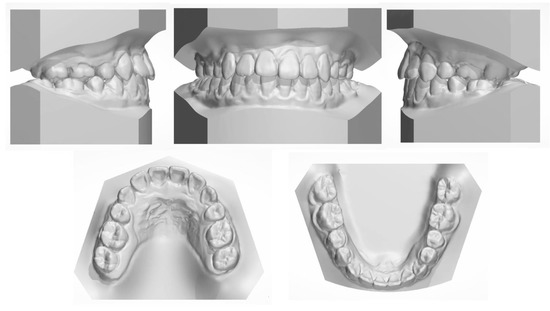

Figure 2. The pretreatment dental cast.

The facial examination displayed a concave profile, a prominent chin, an increased lower third of the face, and an unconfident smile. The upper lip was retruded 4.8 mm in relation to the E plane (Figure 1). The intraoral photographs (Figure 1) and dental casts (Figure 2) showed a bilateral Class III molar relationship and an anterior crossbite with a negative overjet of 2 mm. The width of the maxilla was narrow compared to the mandible, which led to a crossbite in the right posterior region and a compensatory lingual inclination in the left mandibular posterior region. All the mandibular deciduous molars and maxillary deciduous canines were retained with the left permanent maxillary canine erupted labially. Scalloped thin gingiva was evident in the mandibular anterior region with an obvious root shape. Temporomandibular disorder symptoms or bad oral habits were not detected. The mandible cannot retreat to the edge-to-edge occlusion.

The panoramic radiograph showed that both the maxillary canines and all the third molars were impacted, and no significant periodontal support loss was found. The cephalometric analysis (Figure 3 and Table 1) showed a severe skeletal Class III relationship (ANB, −4.0°) with an insufficient developed maxilla (SNA, 77.2°). The maxillary incisors were relatively well-positioned, while the mandibular incisors were lingually inclined (U1-SN,104°; L1-MP, 86.5°) [8].